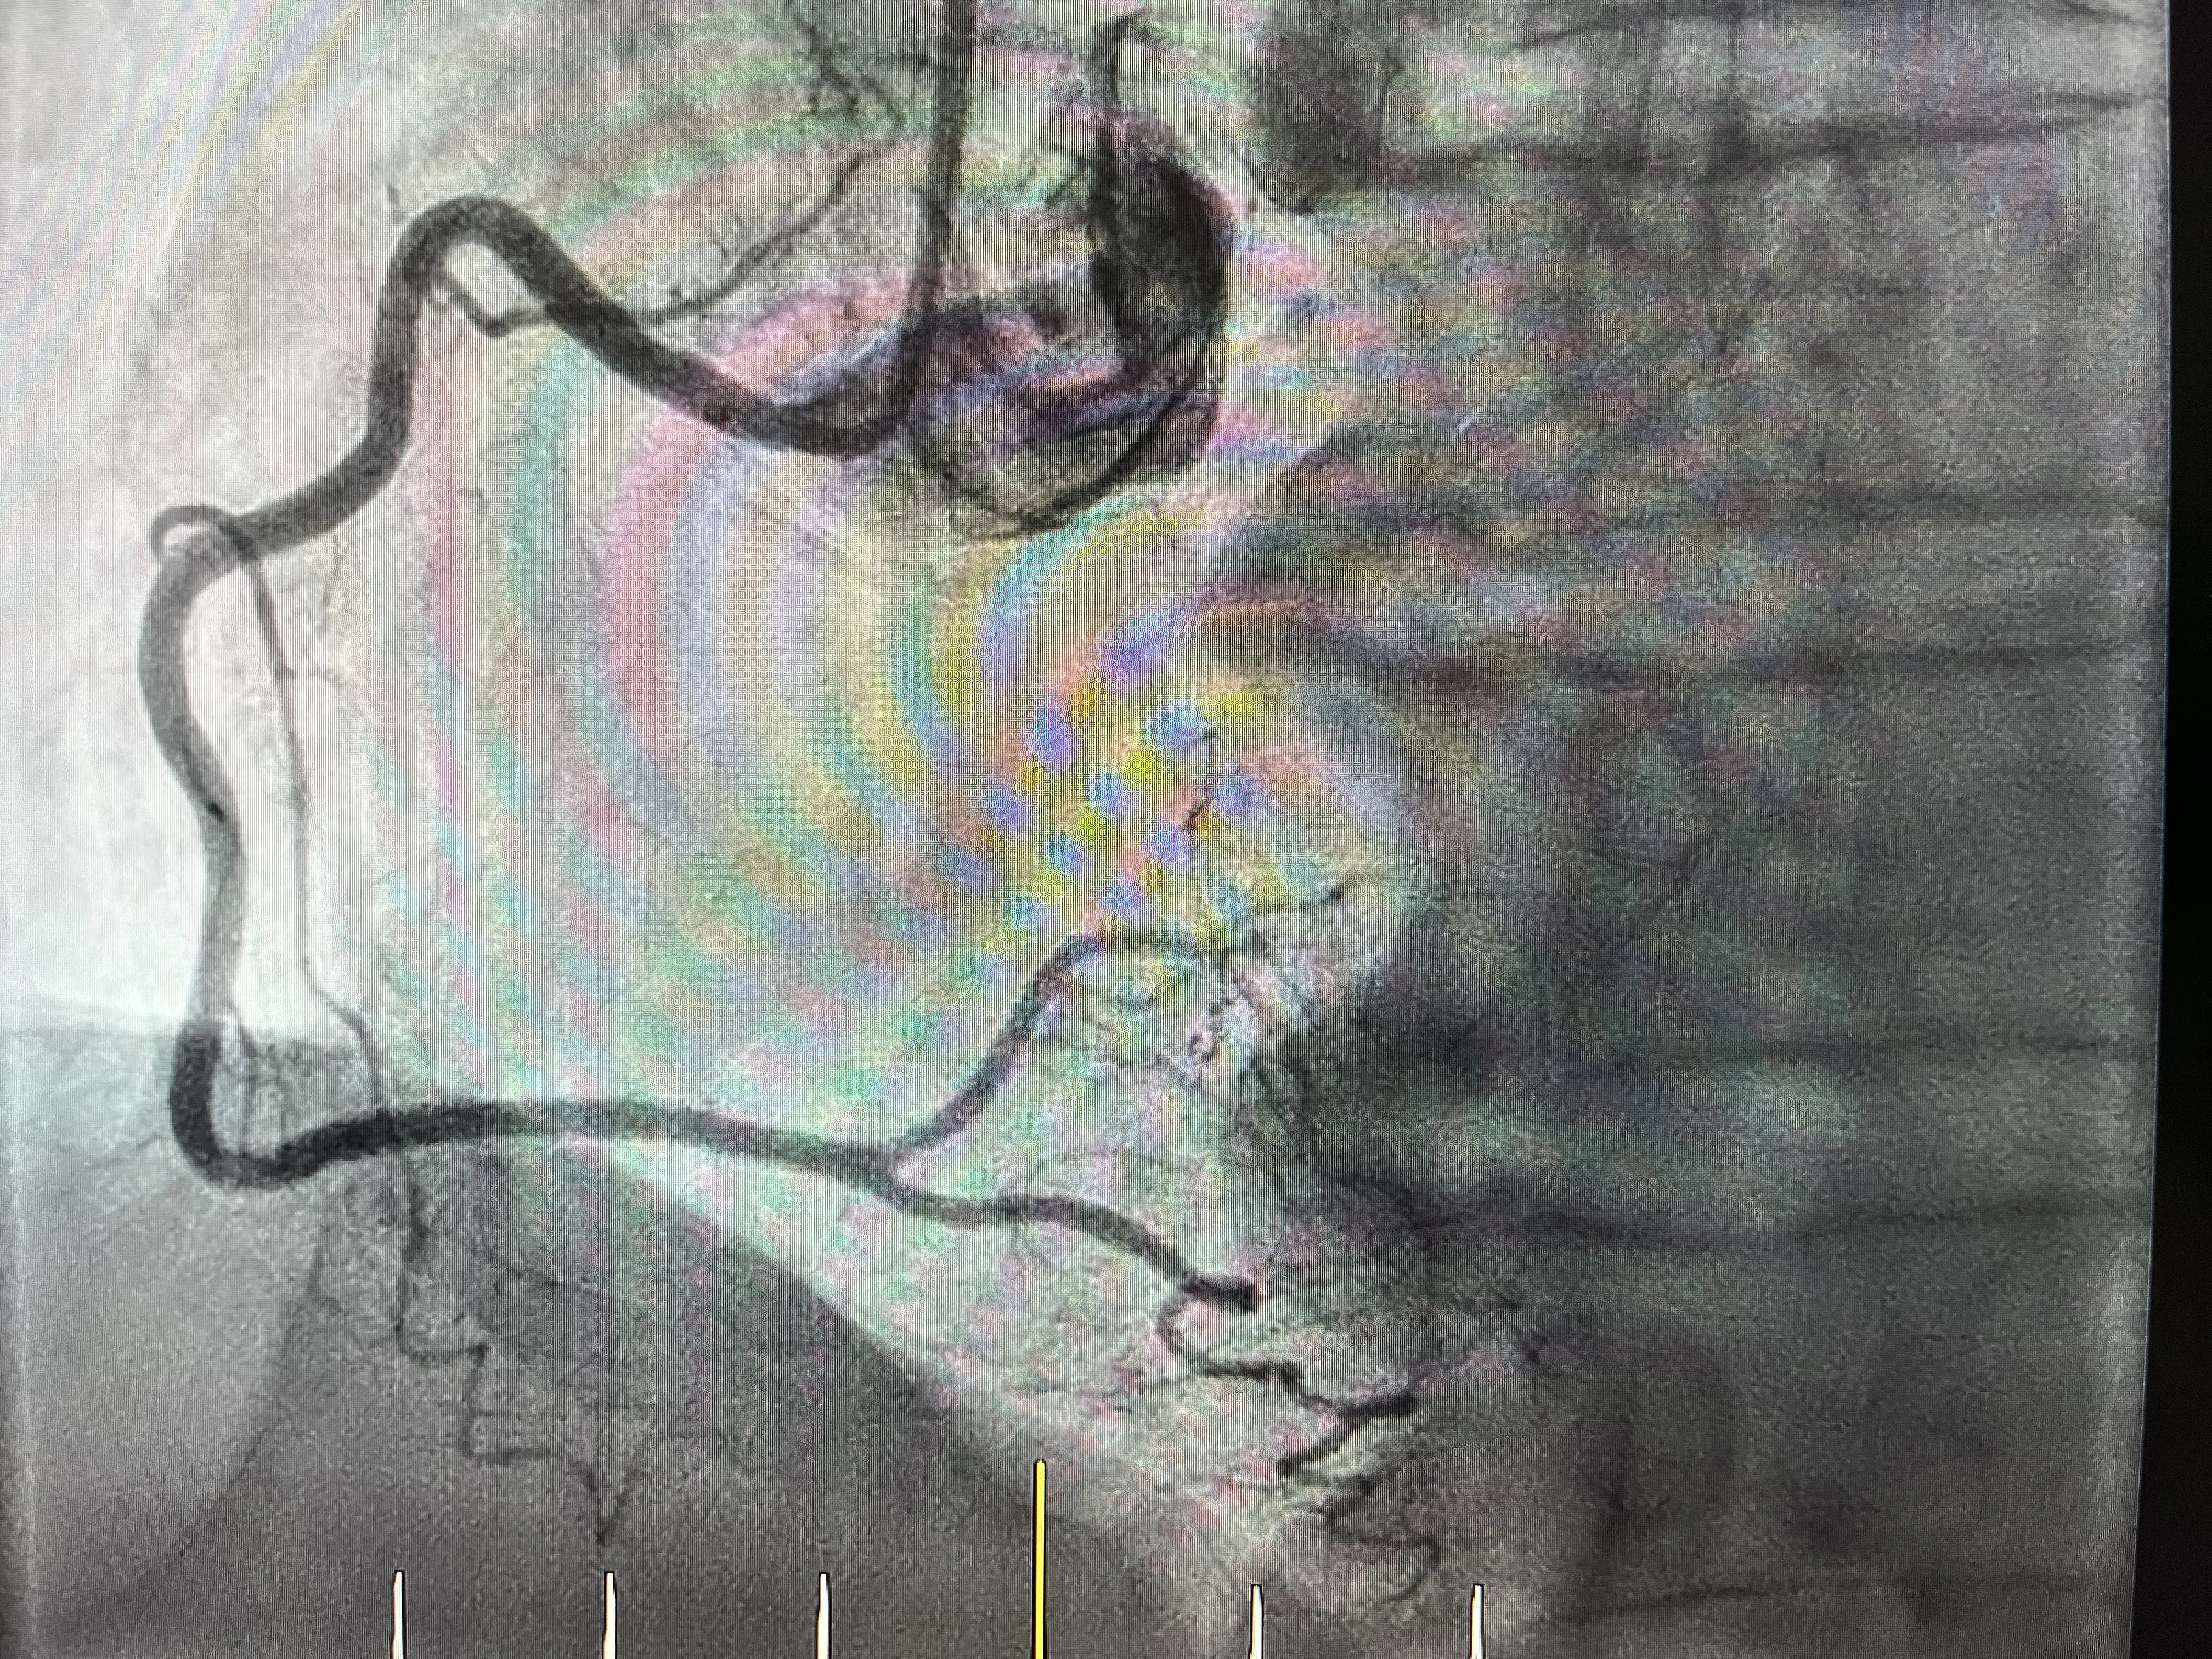

La importancia de la ventriculografía en el Takobsubo

Ante la ausencia de lesiones coronarias significativas, el equipo médico decide dar un paso más y realizar una ventriculografía. Esta prueba permite ver cómo se mueve el ventrículo izquierdo y detectar alteraciones en su contractilidad que no se explican por una obstrucción coronaria. En el contexto de un posible Takobsubo, la ventriculografía se vuelve fundamental para confirmar la sospecha y entender la mecánica del problema.

En el caso concreto de este paciente, la ventriculografía fue la que aportó la pieza que faltaba en el puzzle. Al observar el movimiento del ventrículo izquierdo, se pudo ver claramente que no se comportaba de forma homogénea. Había una zona que se movía menos de lo esperado, lo que ya orientaba hacia una disfunción segmentaria típica de este síndrome. Sin esta prueba, probablemente el caso habría quedado como un dolor torácico atípico con coronarias sanas.

La ventriculografía no solo sirve para describir una hipoquinesia, sino también para visualizar la forma global que adopta el ventrículo durante la sístole. En el Takobsubo, esa forma característica recuerda a un jarrón japonés, lo que ayuda a darle un nombre muy gráfico al cuadro. Por tanto, esta prueba no es un mero complemento, sino una herramienta clave para pasar de la sospecha a un diagnóstico mucho más concreto y explicativo.

Hipoquinesia inferior del ventrículo izquierdo

En la ventriculografía de este paciente se observó una hipoquinesia inferior del ventrículo izquierdo, es decir, que la parte inferior de esa cavidad se movía poco. Esta disminución del movimiento no se correspondía con una lesión en una arteria concreta, porque ya se había visto que las coronarias estaban sanas. Esa discordancia entre la anatomía coronaria y la función ventricular es muy típica del Takobsubo y ayuda a diferenciarlo de un infarto clásico.

La hipoquinesia inferior implica que esa zona del ventrículo no contribuye de forma normal al bombeo de sangre, lo que puede explicar parte de los síntomas del paciente. Aunque no haya una arteria obstruida, el corazón no está funcionando de manera homogénea y eso se traduce en malestar y en una sensación muy similar a la de un infarto. Es una forma de sufrimiento miocárdico que no encaja en el esquema tradicional de daño por falta de riego.

Este hallazgo de hipoquinesia inferior, unido a la ausencia de lesiones coronarias significativas, encaja muy bien con el patrón del Takobsubo. No se trata de un problema localizado en una arteria, sino de una alteración funcional del ventrículo que adopta una forma característica. Ver esa zona inferior moverse poco es una pista clave que, junto con el resto de datos, permite al equipo médico orientar el caso hacia este diagnóstico tan particular.

La imagen típica de jarrón japonés

Cuando se observa el ventrículo izquierdo en la ventriculografía de un Takobsubo, la imagen global recuerda a un jarrón japonés, y de ahí viene precisamente el nombre. En este caso, la hipoquinesia inferior contribuye a que la cavidad adopte esa forma peculiar, con una parte que se mueve menos y otra que se contrae de manera diferente. Esa silueta tan característica es lo que ha hecho que se asocie este síndrome con el famoso jarrón japonés llamado Takobsubo.

La comparación con un jarrón no es solo una metáfora bonita, sino una forma muy visual de entender lo que está pasando en el corazón. En lugar de contraerse de forma uniforme, el ventrículo se deforma y genera una imagen que se aleja de la forma habitual que se espera ver. Esa deformación es la que hace que, al mirar la ventriculografía, uno piense inmediatamente en ese recipiente japonés y asocie la imagen con el diagnóstico.

En el caso que comento, la ventriculografía mostró precisamente esa apariencia de jarrón japonés, lo que terminó de confirmar la sospecha de Takobsubo. No es solo que el ventrículo se mueva raro, sino que lo hace de una manera tan típica que casi se podría reconocer el cuadro solo por la forma. Esa imagen, sumada a la clínica y a las coronarias sanas, cierra el círculo y permite hablar con bastante seguridad de la enfermedad del jarrón japonés.

Durante el cateterismo se comprobó que la arteria coronaria derecha no tenía lesiones significativas y que la coronaria izquierda tampoco mostraba enfermedad relevante. Ante este hallazgo, el equipo médico decidió no quedarse solo con la tranquilidad de unas coronarias sanas, sino ir un paso más allá y hacer una ventriculografía. Fue en esa prueba donde se observó la hipoquinesia inferior del ventrículo izquierdo y la imagen típica de jarrón japonés asociada al Takobsubo.